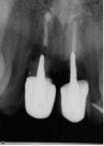

The patient, a 13-year-old female, was seen for emergency treatment in July 2005. The child was catapulted over the handlebars of a bicycle, resulting in the avulsion of the right and left permanent maxillary central incisors. The avulsed teeth were left dry in the palm of her hand for 10 minutes until she reached the hospital where the teeth were placed in milk. Other oral injuries included a laceration on the right side of the philtrum, which was sutured. Examination of the avulsed teeth revealed that the crowns were intact but the mesial incisal edges of both were fractured. Treatment options were explained to the parents and replantation of the avulsed teeth was chosen. She was referred to a local dentist to have the teeth replanted. The roots of the teeth were planed to remove any debris and were then reinserted into the alveolar socket and secured with a splint for six weeks. During the next year the patient had root canals done, followed by metal posts and PFM crowns placed on the avulsed teeth (Figure 1).

Due to the patient’s age at the time of trauma, the crowns were replaced five years later with lava crowns, which are porcelain crowns with a zirconia framework inside (refer to figure 2a and 2b).